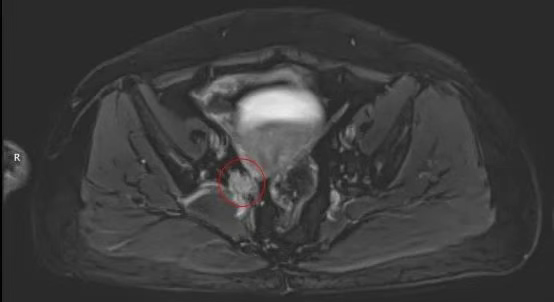

2.影像检查

腹盆腔MRI:1.宫颈部异常强化软组织信号,符合宫颈癌表现(I期),盆腔内小淋巴结,请结合临床。 2.左下腹部囊性灶,来源待定,请结合临床,建议复查。 3.肝脏多发囊肿,脂肪肝。 4.左肾错构瘤,双肾多发囊肿。 5.盆底少量积液。

治疗前